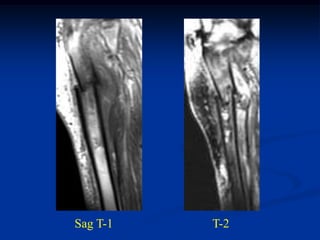

Case #7               Jan 6   Feb 2

Adult Intestinal

Osteomalacia

49 yr female with

severe obesity and

gastric bypass 2 yr

ago and now recent

gradual onset of

pain in leg without

trauma

Isotope bone scan

Cor T-1              T-2                Gad

Increased alkaline phosphatase and PTH levels

Sag T-1   T-2